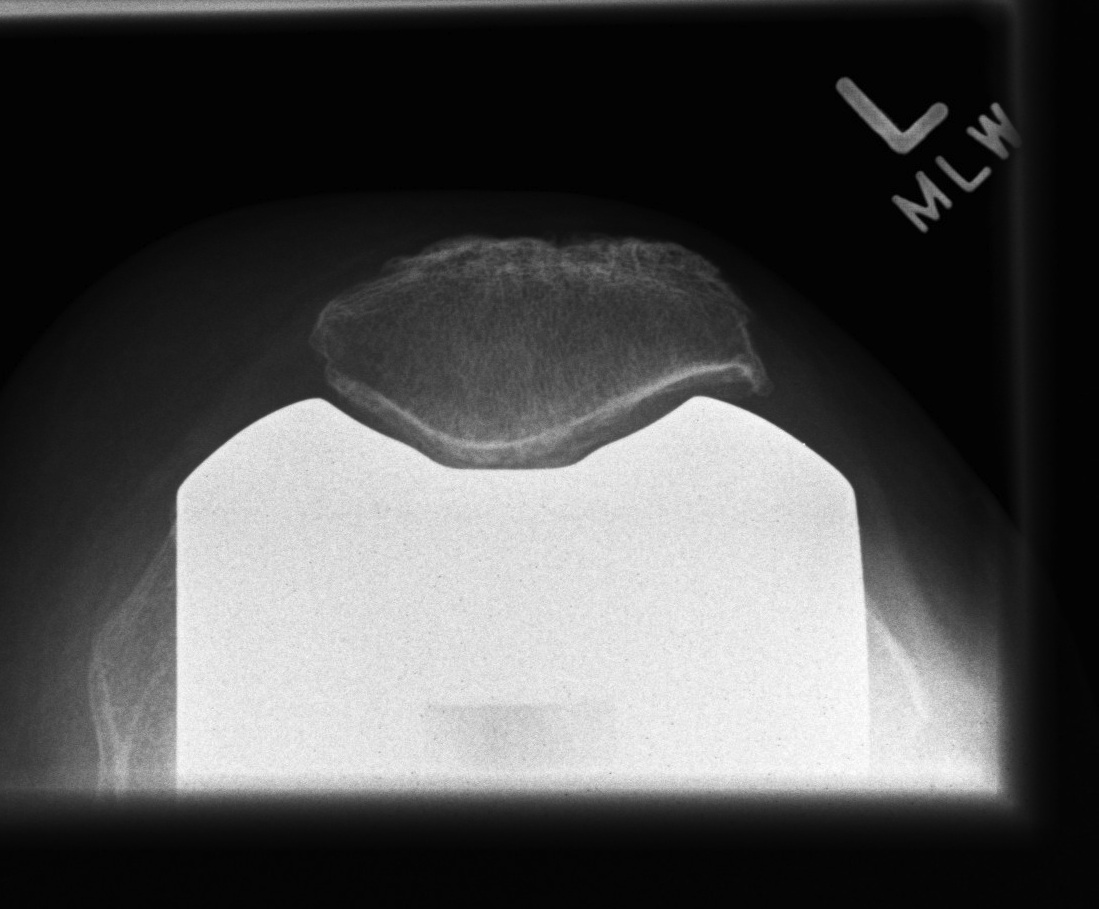

Patella Prosthetic Design

Metal Backing of Patella

- good fixation to bone

- but thin poly, getting wear and catastrophic failure

- poly can detach from metal

- out of favour

Anatomic patella

- no central plug

- femoral prosthesis deep conforming patellar groove & raised lateral flange

Central Dome

- most adaptive with least congruity

- button

- most common

Polyethylene